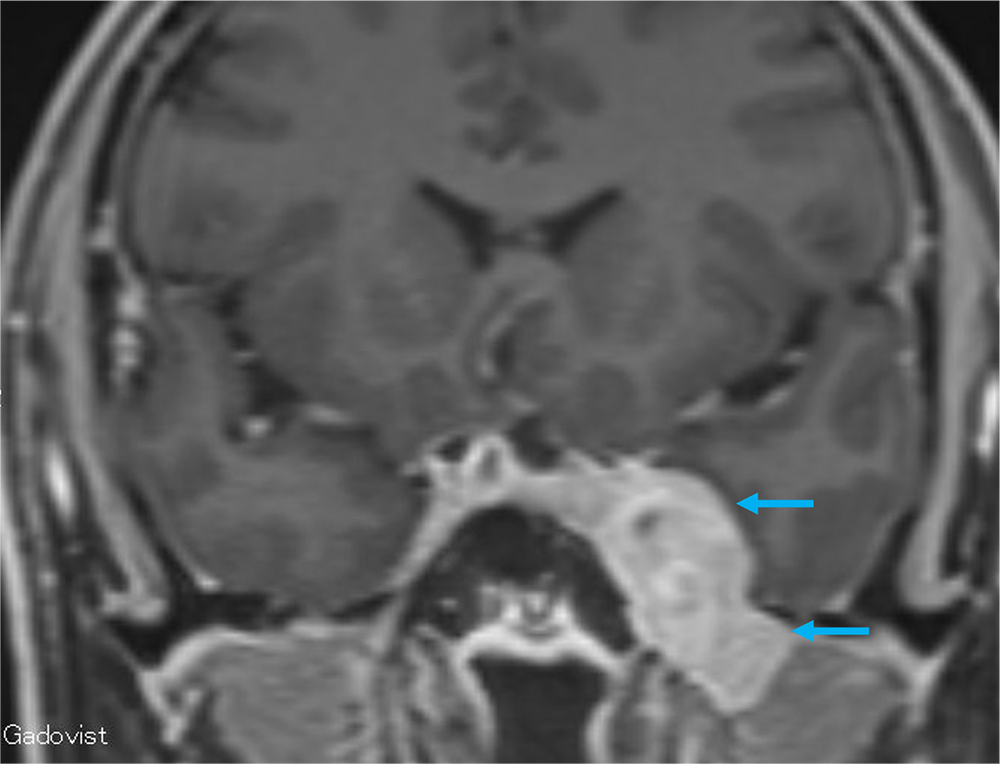

単純MRIのT2強調画像では左メッケル腔から背側に突出する腫瘍を認め、三叉神経鞘腫と髄膜腫が鑑別となる。Gd造影剤の脂肪抑制T1強調画像では腫瘍は全体に濃染し、冠状断では卵円孔を介した頭蓋外進展が見られ、三叉神経鞘腫の可能性が高い。内側では海綿静脈洞を圧排、背側では橋の軽度圧排も見られる。有症状であり、手術が施行され、三叉神経鞘腫と診断された。

当該疾患の診断における造影MRIの役割

三叉神経鞘腫を確実に診断するためには、神経走行に沿った進展を確認することである。Gd造影剤を用いた3Dの脂肪抑制T1強調画像を撮影することで、thin sliceの造影CTと同様に後から再構成したMPRを作成するにより、腫瘍の進展方向を確実に診断することが可能であり、本症例には必須のシーケンスと思われた。